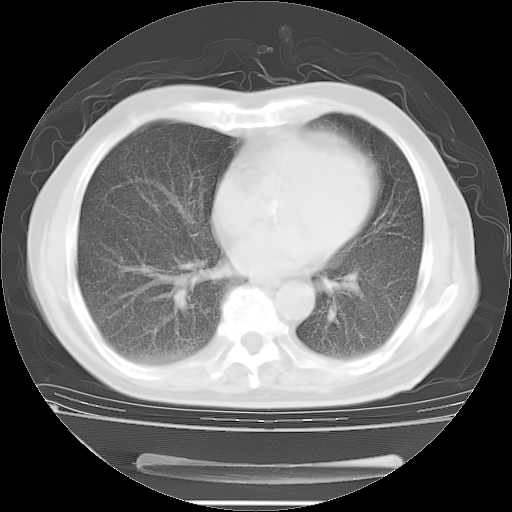

今天复查肺部CT,发现双肺广泛磨玻璃样改变。所以我把3月19日和5月9日相隔50天的肺部CT上传。请大家会诊。

2009年3月19日肺部CT片。

2009年3月19日肺部CT